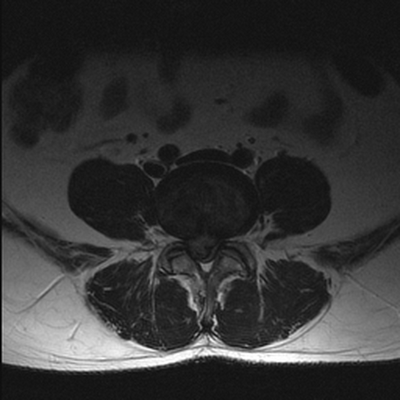

Грыжа диска между телами 4 и 5 поясничных позвонков на МРТ